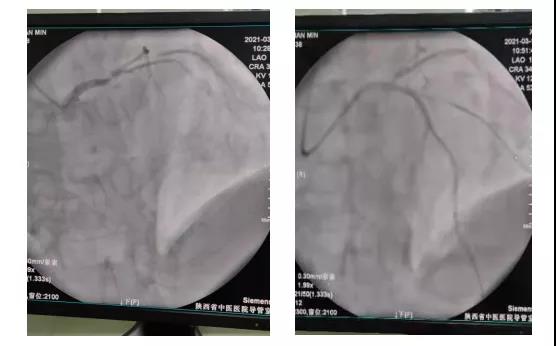

患者进入导管室,除颤仪、抢救车早已到位,消毒、铺巾、穿刺一气呵成。造影提示前降支开口闭塞,导丝迅速通过闭塞的前降支,并于前降支近段植入支架一枚,患者血流恢复,胸痛症状明显缓解。下图为患者冠脉造影结果:LAD开口闭塞,D1狭窄80%,LCX近段狭窄80%。

前降支(LAD)支架植入术前与术后